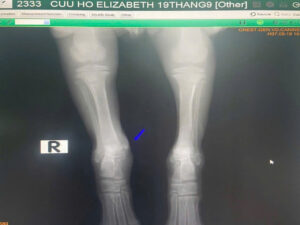

Little Grace had accident. The ankle was wounded and dislocated.

X ray. Replace the bone back to joint. Cast. Treated the infection and inflamation. Strictly care for 21 days.